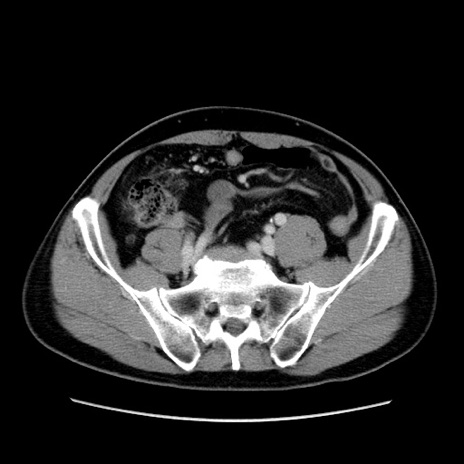

症例34(横断像)

【症例】60歳代 男性

【主訴】右鼠径部膨隆

【現病歴】1年程前より右鼠径部膨隆あり。自己にて還納可能だったため放置していた。3時間前より右鼠径部の脱出を認め、還納困難となり受診。

【身体所見】右鼠径部に小児頭大の膨隆あり。弾性硬であり、用手還納は困難。左鼠径部にも膨隆を認める。脱出はなし。